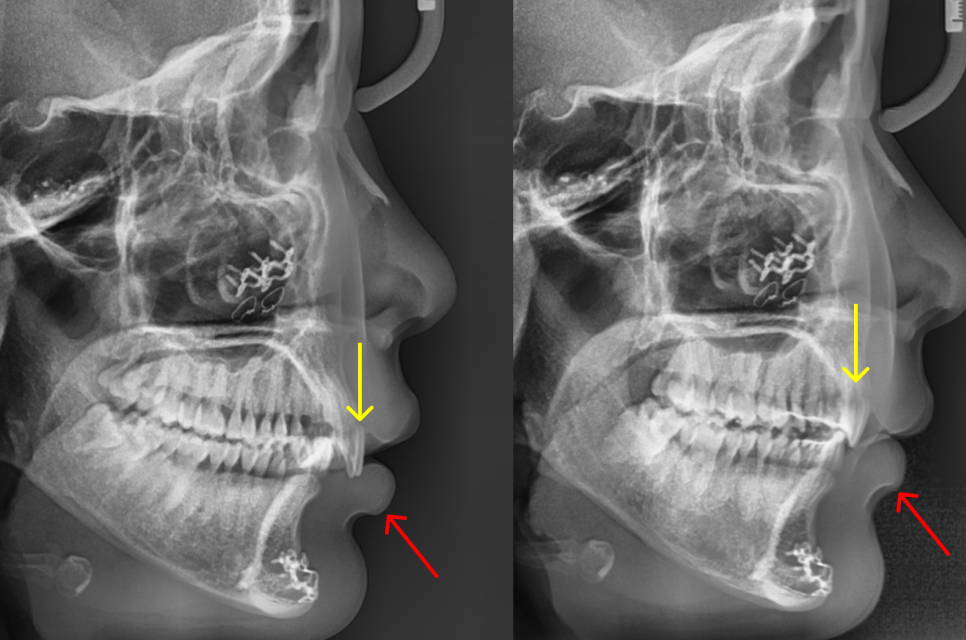

엑스레이를 보면 윗니(파랑)가 아랫입술(노랑)을 누르고 있습니다.

아랫니(빨강)은 보통 사람과 다르게 윗니의 (중간부분이 아닌) 뿌리와 닿아 있습니다.

엑스레이에서 옆모습 변화를 비교하면 이는 더 드라마틱합니다. 앞니(노랑색)가 안쪽 위로 올라가면서 원래 입술(붉은색)을 누르고 있던 현상이 완전히 사라졌습니다. 이에 따라 돌출입 느낌은 완전히 사라졌으며, 특히 힘을 뺀 상태에서 자엽스럽게 입술이 다물어지게 되었습니다.

앞니(노란색)의 이동에 따라, 입술(붉은색)이 완전히 제자리를 찾았습니다.

돌출입이 형태가 사라졌으며, 자연스럽게 입술이 다물어집니다.